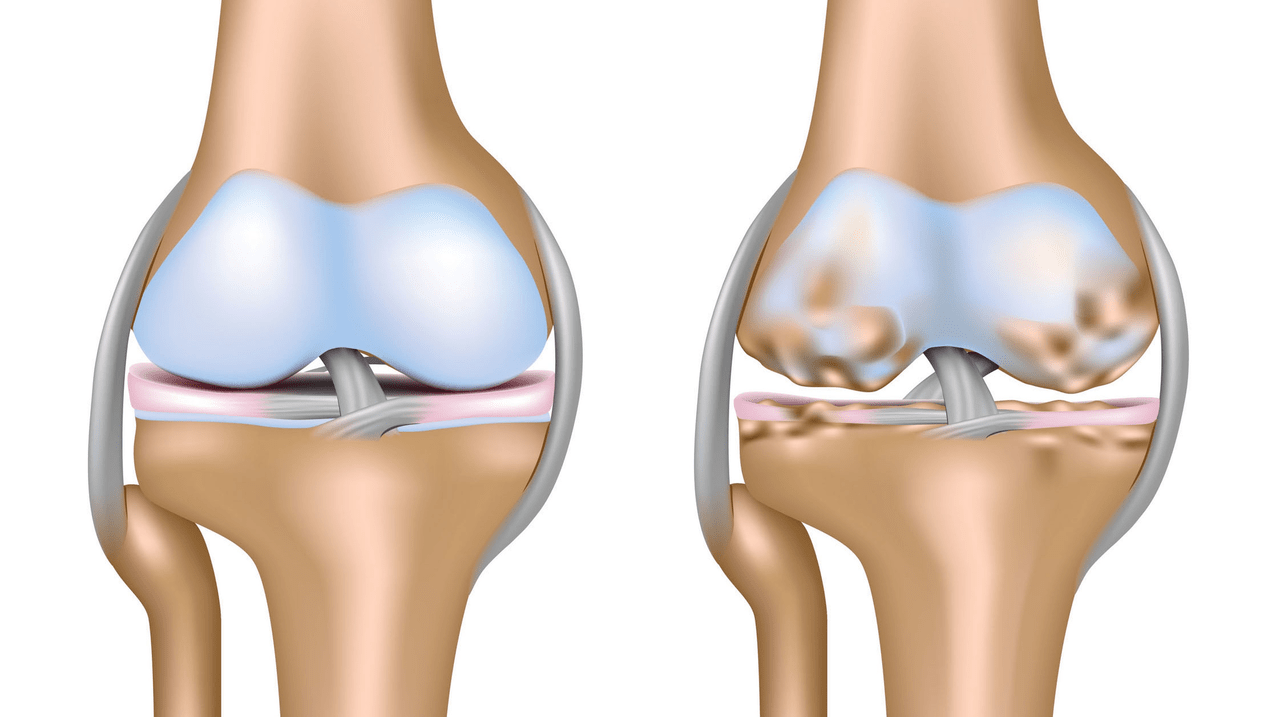

Osteoarthritis of the knee joint (gonarthrosis)is a chronic progressive disease of the knee joints with damage, thinning and destruction of their cartilaginous part (articular surfaces of the femur and tibia), as well as damage to the subchondral bone.It has been shown through studies (arthroscopy and magnetic resonance imaging) that, in addition to damage to the articular cartilage, the menisci and synovial membrane are involved in the process.Gonarthrosis is one of the most common orthopedic pathologies.There are its synonyms: osteoarthritis (OA), deforming osteoarthritis.The disease is an important socioeconomic problem, since it is widespread and significantly worsens the quality of life of patients due to constant pain and, in addition, becomes a cause of great disability.

Until the mid-eighties of the last century, there was no unified definition of the disease.It was not until 1995 that the osteoarthritis committee of the American College of Rheumatology characterized the disease as the result of mechanical and biological factors that lead to an imbalance between the degradation and synthesis processes of the extracellular matrix of articular cartilage.As a result, disintegration and degeneration of fibers occur, cracks, osteosclerosis and compaction of the cortical layer of the subchondral bone form, osteophytes grow and subchondral cysts form.

In osteoarthritis (osteoarthrosis), in addition to the progressive destruction of cartilage, the loss of its elasticity and shock-absorbing properties, the bones gradually become involved in the process.Under load, sharp edges (exostoses) appear, which are mistakenly considered "salt deposits";In classic osteoarthritis, salt deposition does not occur.As osteoarthritis progresses, it continues to "eat away" the cartilage.Then the bone is deformed, cysts form there, all joint structures are affected, and the leg bends.

In the second stage, the cartilage layer becomes much thinner and, in some places, disappears completely.Osteophytes appear along the edges of the articular surfaces.The qualitative and quantitative characteristics of the synovial fluid of the joint change: it becomes thicker and more viscous, which leads to a deterioration of its nutritional and lubricating properties.The pain is longer and more intense, and a crunching sound usually appears when moving.Mild or moderate restriction of movement and slight deformation of the joint occurs.Taking pain relievers helps relieve pain.